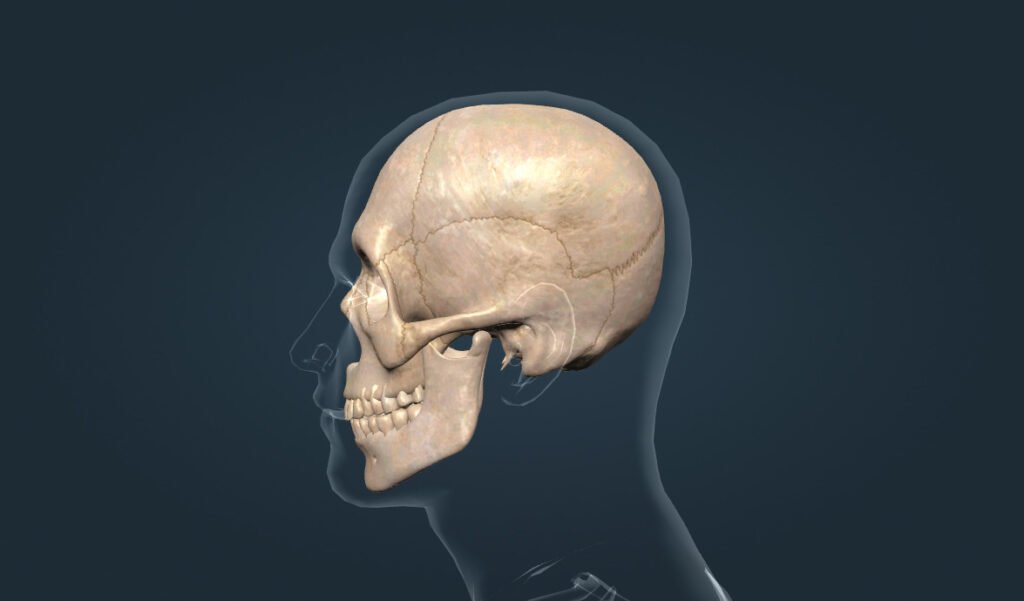

Череп — це кістковий каркас голови, який, по-перше, захищає головний мозок від ударів, а по-друге, підтримує органи чуття. Водночас він створює форму обличчя та забезпечує правильне розташування очей, носа і рота.

Череп складається з двох основних частин, а саме мозкового відділу та лицевого відділу. Кожна з цих частин має свою роль і власні кістки, які разом утворюють міцну конструкцію.

Мозковий відділ черепа оточує головний мозок, тому він є особливо міцним. Крім того, ці кістки з’єднані нерухомо, що забезпечує додатковий захист від пошкоджень.

Лицевий відділ черепа формує риси обличчя та підтримує органи дихання і травлення. Завдяки цьому череп не лише захищає, але й допомагає людині виконувати щоденні дії.

Череп людини складається з 22 кісток, і більшість із них з’єднані нерухомо. Однак нижня щелепа є винятком, адже вона рухома і дозволяє нам жувати та говорити.